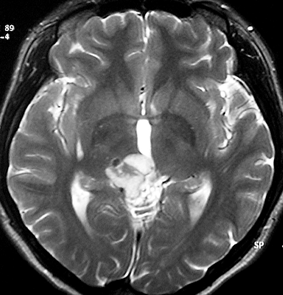

成人男性が早朝の頭痛で発症しました。閉塞性水頭症になっているので第3脳室開窓術が行なわれてから紹介されてきました。開頭手術で全摘出して,病理が PPTID グレード3でしたので,脳脊髄照射 24Gy/12fr と腫瘍局所照射 54Gy/27fr をしました。